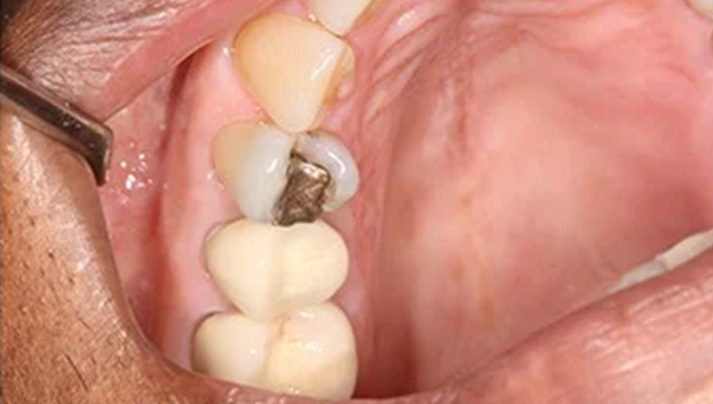

Before and Afters – White Fillings